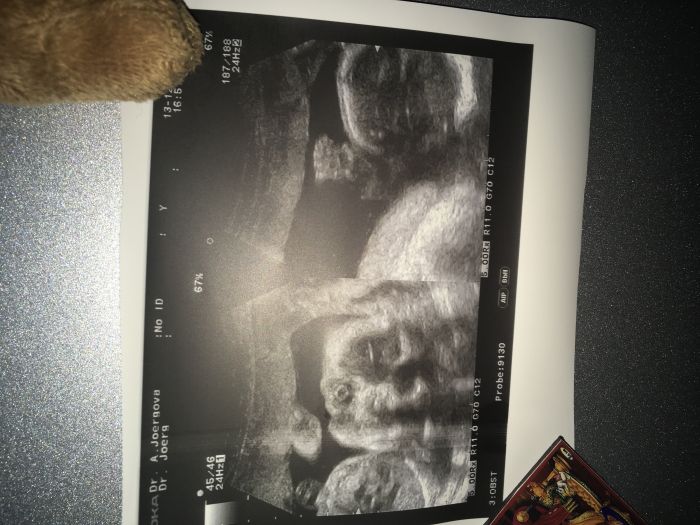

Já včera vůbec nestihala.. poradna dopadla dobře a na 100% kluk. Tentokrát jsem i já viděla toho bimbase a pro jistotu mi ho i vyfotila,ať prý už mě nikdo nemate.

[1046588]tak chlapák nakonec, pěkně napínal

ten náš nám pytlík předvádí pokaždé v plné kráse, že by to viděl i slepý